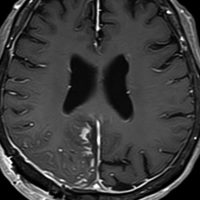

40代男性の大脳鎌テント接合部の硬膜に発生したグレード3です。激しい出血のために腫瘍摘出を部分摘出で中断せざるを得なかった例です。

この例でも,硬膜発生腫瘍ということは手術前の画像診断で解ってはいたのですが,髄膜腫と異なり不整な形をしてのう胞があり,一部は腫瘍壊死でした。